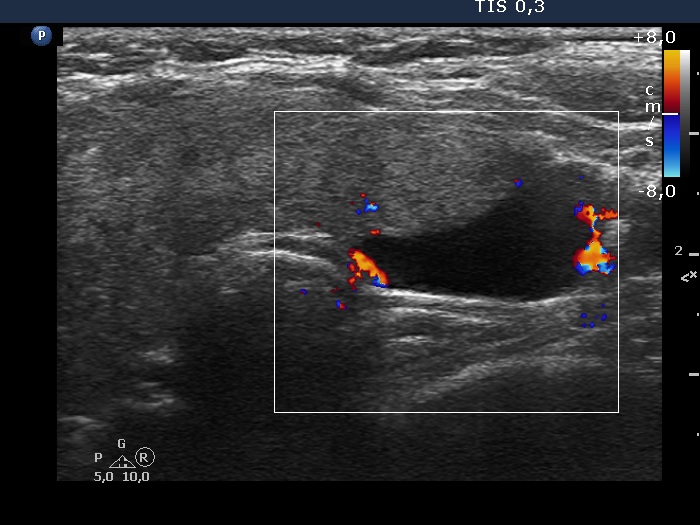

Right lobe, longitudinal scan

Lobe, transverse view, color Doppler mode. There are two vessels at the border of the lesion.